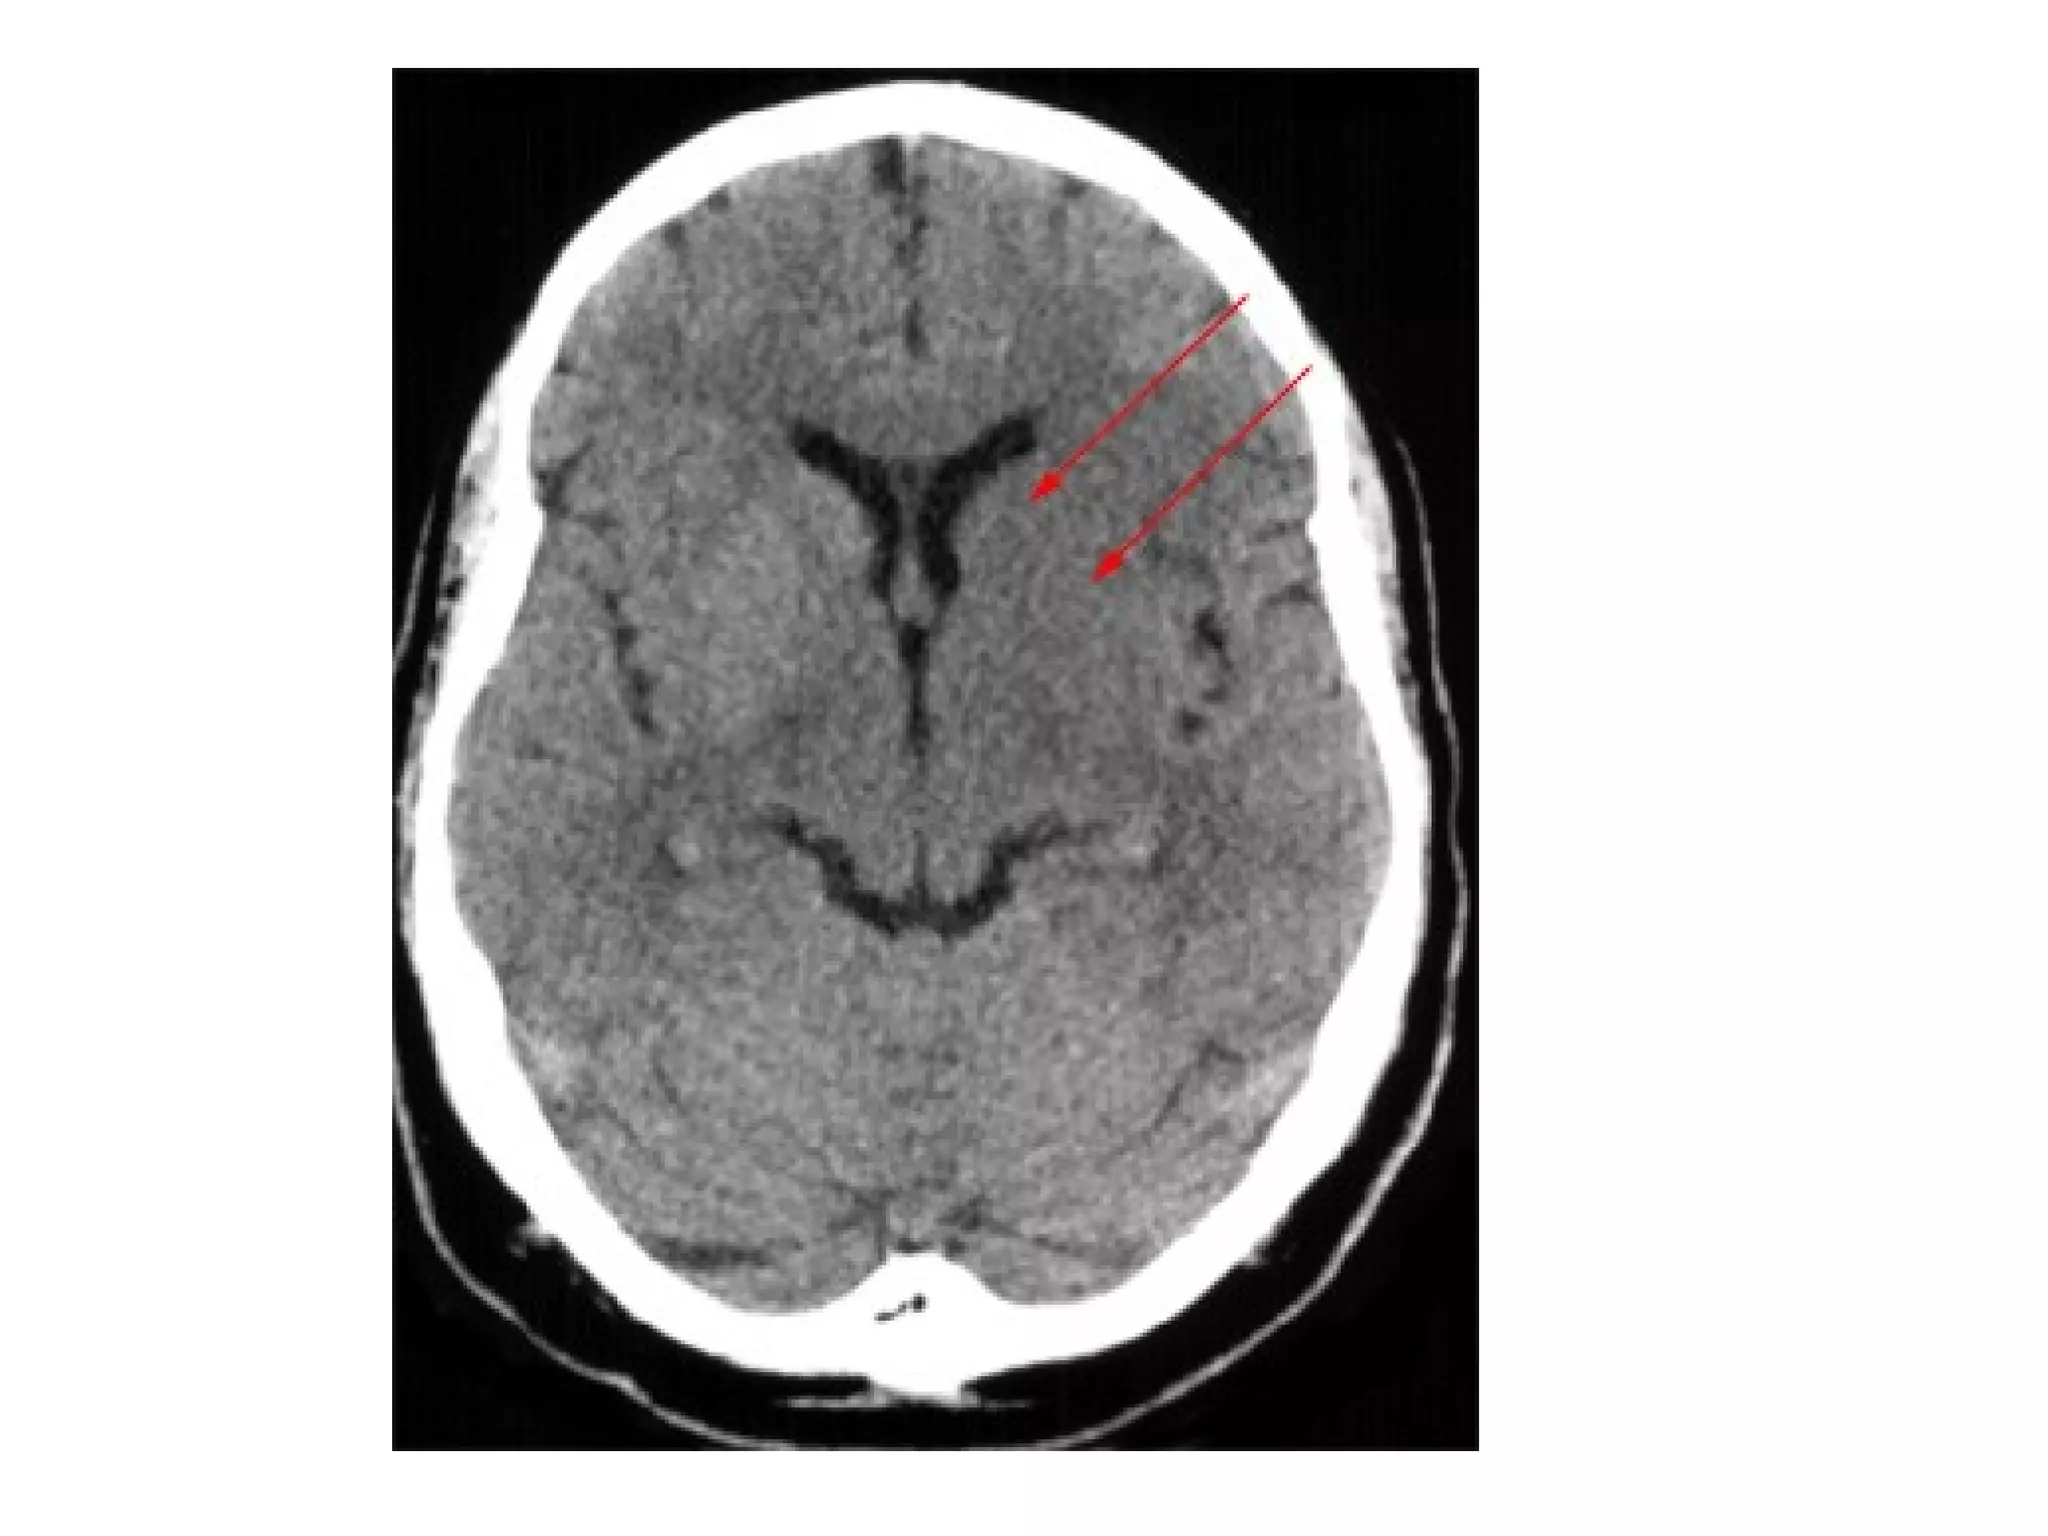

Lateral lenticulostriate infarction , note the inverted comma-shaped

hypodense left lenticular nucleus (red dotted lines) , the anterior limb of

the left internal capsule (yellow arrow) is also involved by the ischemic

infarction while the head of the left caudate nucleus (blue dotted lines) is

spared